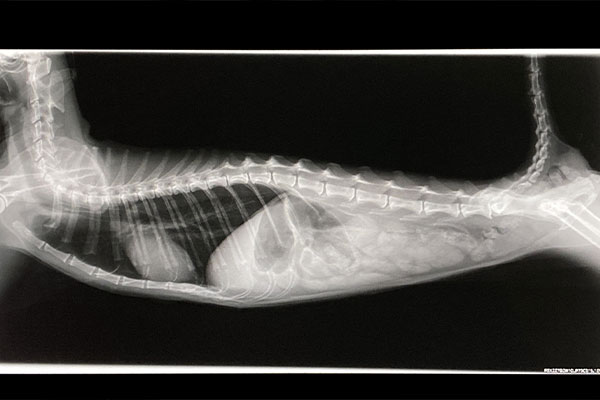

初診では、デジタルレントゲンや超音波画像診断装置など西洋医学の理論でつくられた新しい医療機器を使いながら、東洋医学の「四診」で体全体を診ているため、負担をできるだけ軽く、動物にやさしい診察・検査となっています。

当院では「ペット手帳」というアプリでレントゲンなどの画像や検査報告書などを飼い主の方と共有しています。診察の見える化をすることで、納得のうえ、安心して診察を受けていただけるように取り組みを進め、ご満足いただいています。